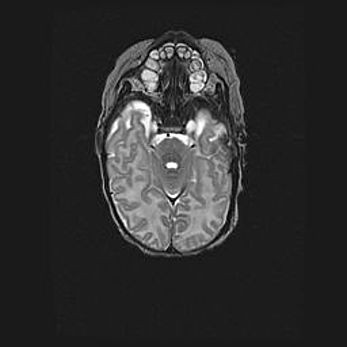

Сообщающаяся гидроцефалия. Кистозная энцефаломаляция головного мозга.

Возраст: 3 месяца 4 дня

Вес: 3100 г

Пол: женский

Окружность головы: 34 см

Срок гестации: 31 неделя

Кистозная энцефаломаляция головного мозга - одна из форм поражения головного мозга в детском возрасте. Характеризуется возникновением множественных и распространённых кист в коре, белом веществе и подкорковых образованиях головного мозга у плодов, новорождённых и детей раннего возраста. Развитие кистозной энцефаломаляции связано с внутриутробной асфиксией и гипотонией, родовой травмой, тромбозом синусов, пороками развития сосудов, инфекциями, сепсисом и другими причинами. Наиболее значимые инфекционные агенты: вирусы простого герпеса, цитомегалии, краснухи, токсоплазмы, энтеробактерии, золотистый стафилококк и другие.